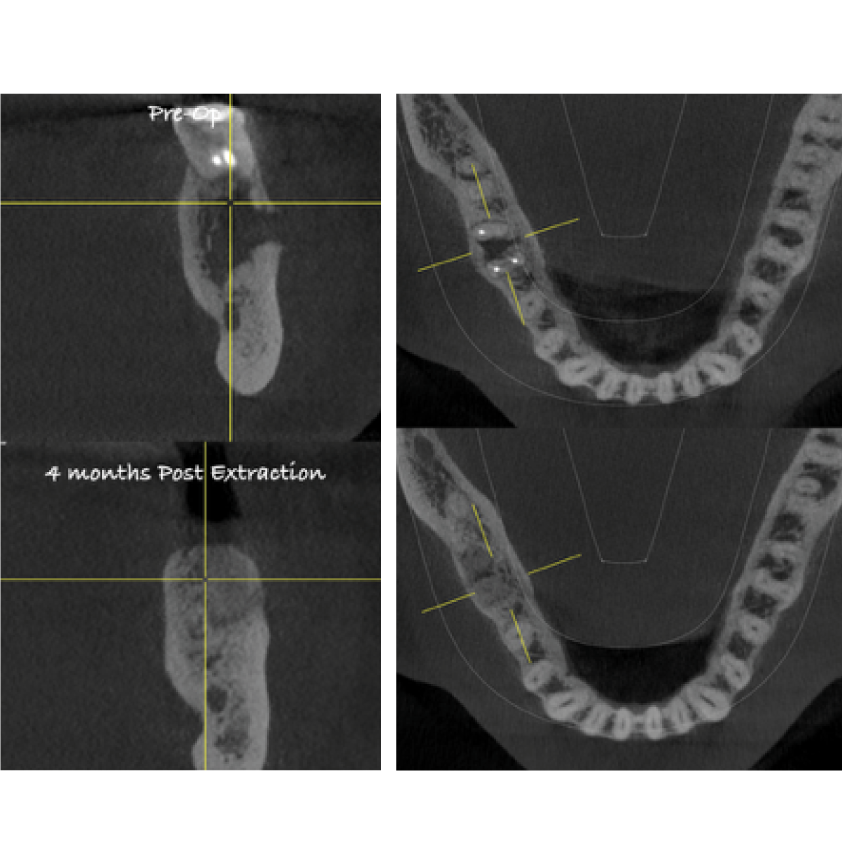

Director’s Clinical Cases

Director’s Clinical Cases